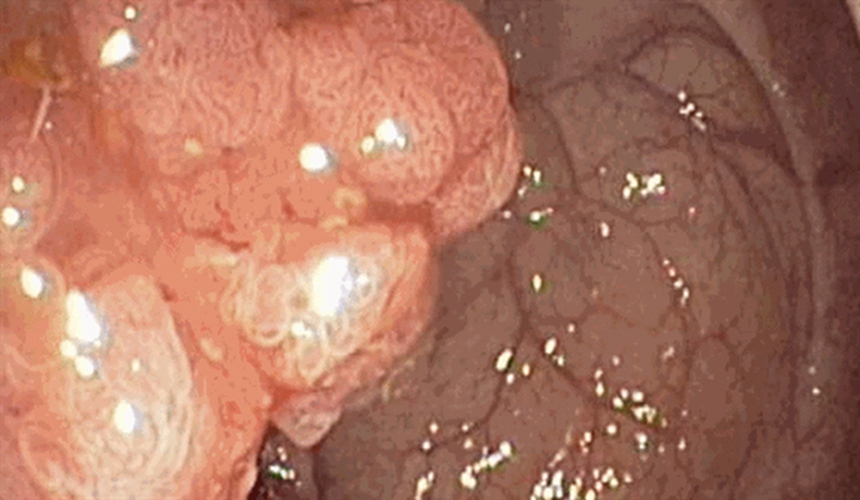

右半結腸癌腺癌一級